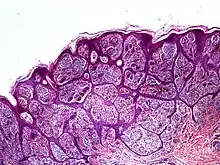

Nevoid melanoma is a cutaneous condition that may resemble a Spitz nevus or an acquired or congenital melanocytic nevus.[1]